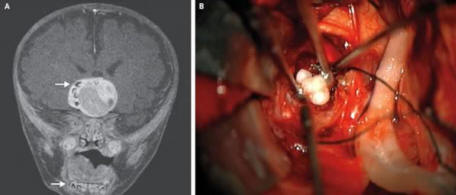

Marylandin 4 kuukauden ikäinen vauva voi olla ensimmäinen henkilö, jonka aivoissa oli kasvain, joka osoittautui hampaiksi. Ensimmäistä kertaa lääkärit epäilivät, että jotain oli vialla, kun lapsen pää näytti alkoi kasvaa nopeammin kuin on ikäisille lapsille ominaista.

Aivotutkimus paljasti kasvaimen, joka sisälsi sen rakenteet, jotka muistuttavat hyvin ihmisen hampaita, yleensä löytyvät alaleuassa. Kasvain on poistettu ja nyt poika tuntuu itse hyvin.